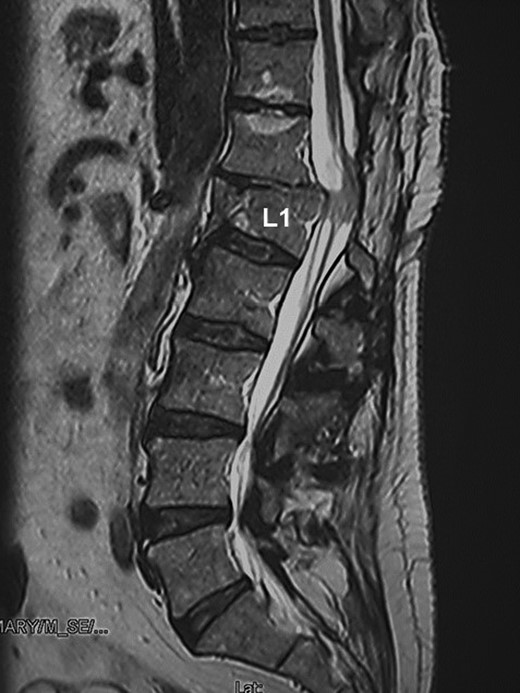

A 58-year-old man with an incomplete SCI (ASIA C and neurological level at Th12) secondary to L1 vertebral fracture (Fig. 1), presented a 32-year history of gait disorder with neurogenic bowel and bladder dysfunction.